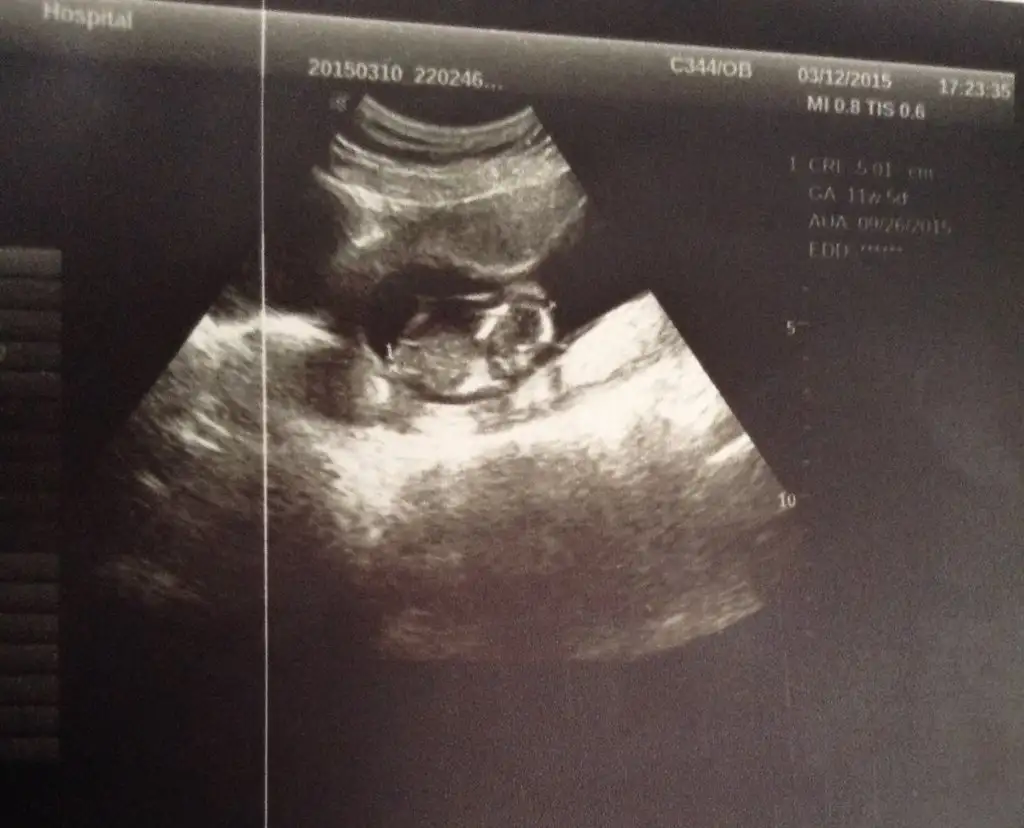

Baska doktora gittKızlar buda bugün çekildi doktor bişey diyemedi çünkü tam orda kordon geçiyo nedesem yanıltırım dedi kordon olmasaydı söyleyecekti of yaaaa

Artık ay sonu gibi giderim ya sıkıldım git gel bişeyde demiyolar ben iki oğlumuda 12 haftalık ken gördüm dedim doktora oda erkek söylemek kolay dedi ama buna erkekte desem yanılırım çünkü kordonu dolamış ayağına dediBaska doktora gitt